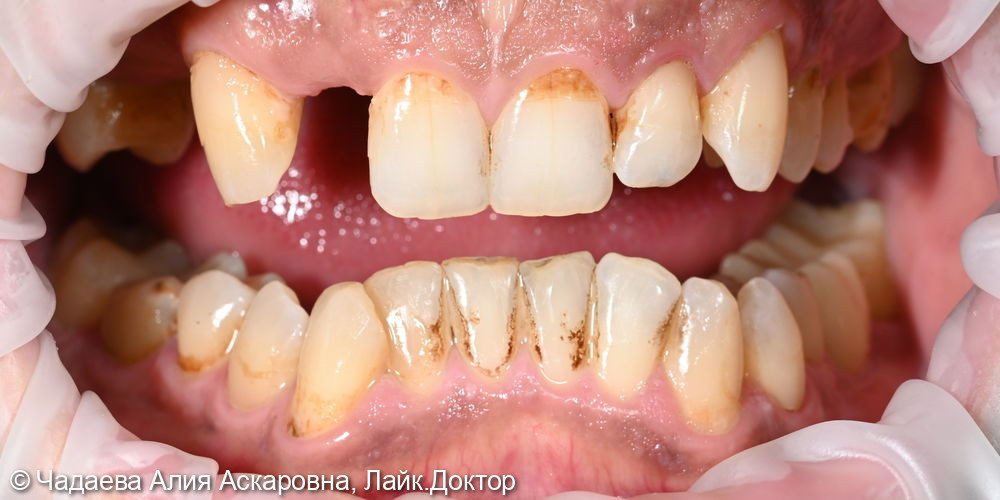

Пациент обратился с жалобами на наличие надесневых зубных отложений и пигментного налета. При проведении осмотра было выявлено наличие надесневых отложений и пигментного налета.

Проведена комплексная профессиональная гигиена полости рта по швейцарскому протоколу GBT. Удаление зубных камней и зубного налета аппаратом Air-flow, полировкаПоказать полностью... зубов, фторирование (покрытие фторлаком).